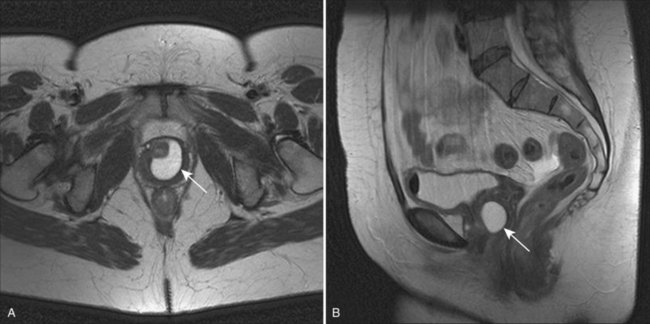

Acquired (also termed “secondary”) diverticula occur most commonly in the setting of bladder outlet obstruction or neurogenic vesicourethral dysfunction. Similar to the congenital type, these diverticula are also located most commonly at the ureterovesical hiatus (Van Arsdalen and Wein, 1992) but also occur elsewhere in the bladder. Acquired diverticula in males usually occur after age 60, which corresponds to the age of the development of prostatic enlargement (Fig. 78–2). Bladder outlet obstructions, including those due to benign and malignant disease of the prostate or urethral stricture, are commonly associated factors in adults, although obstruction is not considered to be present in all cases (Blacklock et al, 1983). Acquired diverticula are often multiple, typically found in association with significant bladder trabeculation (Wesselhoeft et al, 1963), and much more common in males than females (Senger et al, 1952; Pool and Hacker, 1966). Bladder diverticula in females are uncommon (Gillon et al, 1988) and quite rare in the absence of obstruction (Safir et al, 1998) (Fig. 78–3). Historically, the reported prevalence of moderate- to large-sized bladder diverticula in association with “prostatism” is approximately 1% to 6% (Burns, 1944). It is important to note that an acquired bladder diverticulum may also be found in children and young adults secondary to a number of conditions, including bladder neck dysfunction, posterior urethral valves, and neurogenic vesicourethral dysfunction. If the diverticulum encompasses the ureteral orifice in the setting of a neurogenic bladder and vesicoureteral reflux, it is termed a “Hutch” diverticulum (Hutch, 1952). These diverticula may also occur in the setting of dysfunctional voiding.

Figure 78–3 Bladder and urethral diverticula in a female. A, MRI of a bladder diverticulum. B, Endoluminal MRI demonstrating urethral diverticulum (arrow points to urethral diverticulum). B, bladder; D, bladder diverticulum.